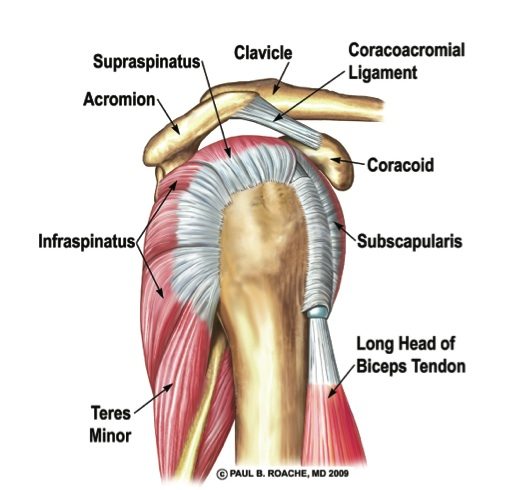

Фотографии мышц ротаторной манжеты плеча